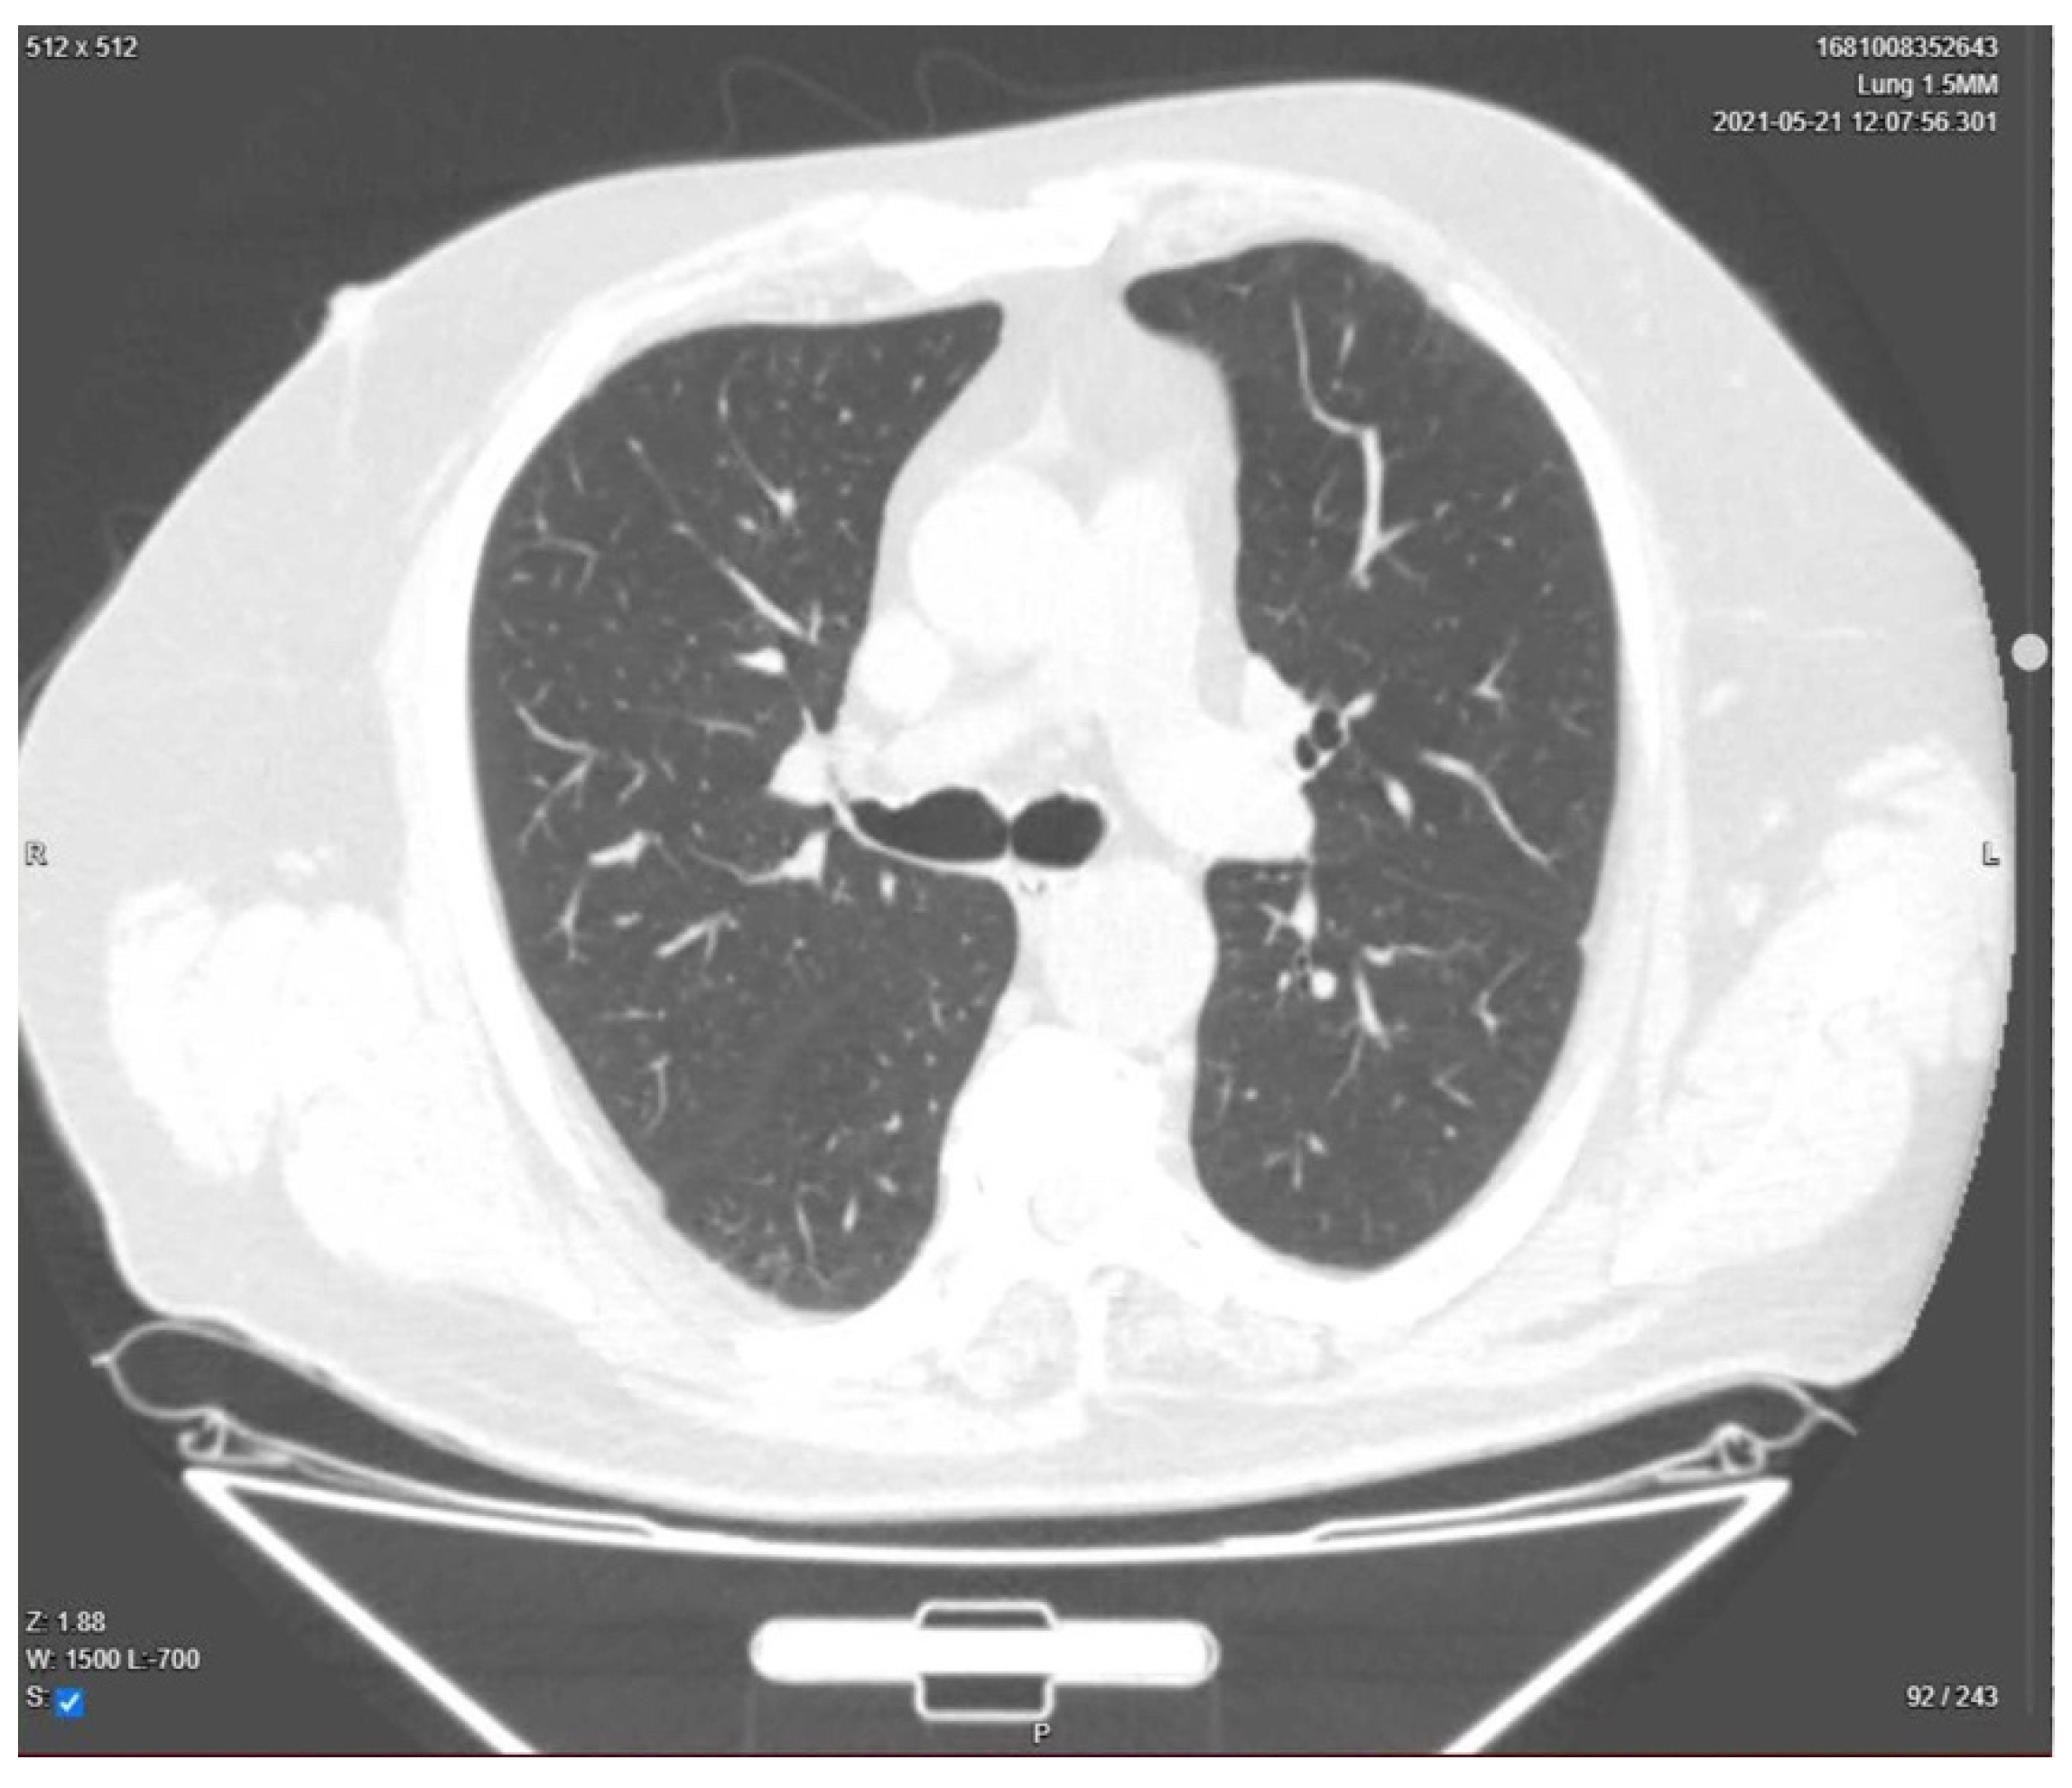

| Day 23 | Lung CT was performed for pulmonary re-evaluation. |

| Day 24 | The patient was discharged home. |